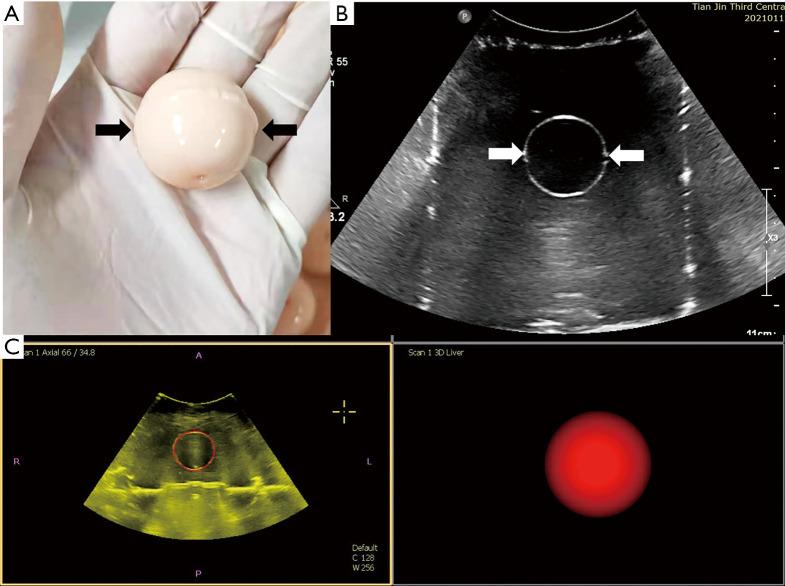

Polyacrylamide gel was mixed with thermochromic ink to produce a phantom model. A phantom model embedded in a tumor model was constructed and used to evaluate the ablation procedure. The phantom models were randomly divided into complete ablation group and incomplete ablation group. The ablation planning of the tumor was on the 3D US and performed on a phantom model. We guide the ablation procedures according to the ablation planning. The results measured in a gross specimen of the phantom model were compared with the expected results in ablation planning.

The color of the model changes from cream white to magenta after heating. The mono-site ablation area is a spheroid after thermal ablation with a size of 3.0×1.8 cm at 60 W, 5 minutes, 3.5×2.5 cm at 60 W, 10 minutes, and 4.0×3.5 cm at 60 W, 15 minutes, respectively. According to the ablation planning, a total of 4 ablation points were needed to retrieve the complete ablation of a 3.0 cm tumor. The complete ablation and incomplete ablation were proved by a gross specimen of the phantom model as we expected.

A novel thermochromic tissue-mimicking phantom model with a spherical tumor model has been designed and developed. The ablation area can be visualized on this phantom model by the permanent color change. This phantom model can assess the ablation planning system's accuracy and train operators for ultrasound-guided thermal ablation.